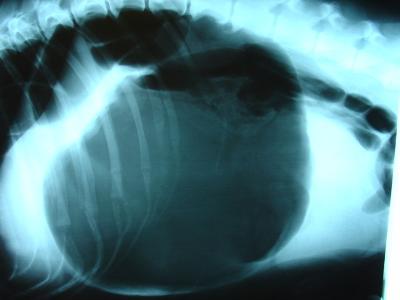

- The left side of the abdomen behind the ribs becomes very distended and very tense, like a drum. Later the right side also becomes distended